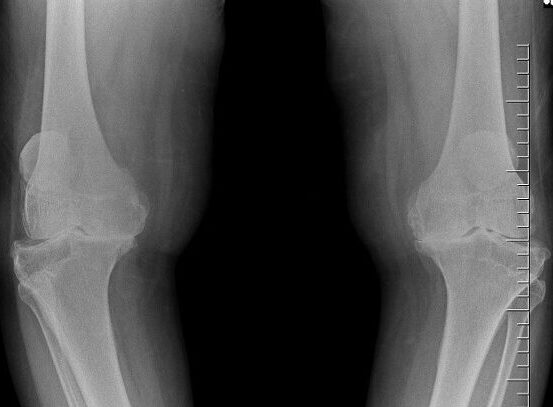

As the time advances may after 1 or 2 years he starts getting x-ray changes in the knee Joint initially in patellofrmoral joints ,then tibiofemoral joint further there after some years still destruction causes the requirement of Knee Replacement Surgery.

Mild Osteoarthritis

X ray picture of the beginning of arthritis Look at the Articular Margins and subluxation of joints

Severe Osteoarthritis

This is the stage when the patient has to depend on some assistant or help for his movements and severe pain

Moderate Osteoarthritis

After 3-4 years approx. Xray Changes still advanced hence the pain and the Disability